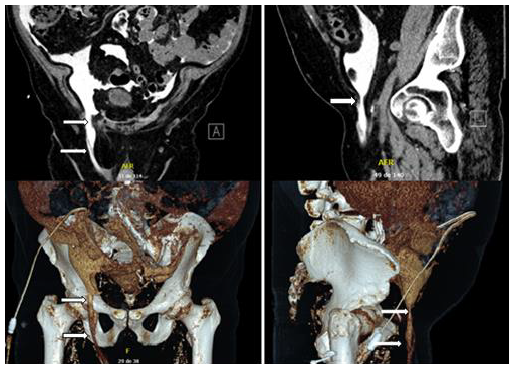

His right IH was treated by open Lichtenstein TFMH (Figure 2), and PD was resumed 4 weeks after the operation. Currently, after 12 months of follow-up, the patient remains recurrence-free while on CAPD due to his preference.

Figure 2.Figure 2. Hernioplasty according to the Lichtenstein technique. a: Polypropylene mesh, b: Spermatic cord